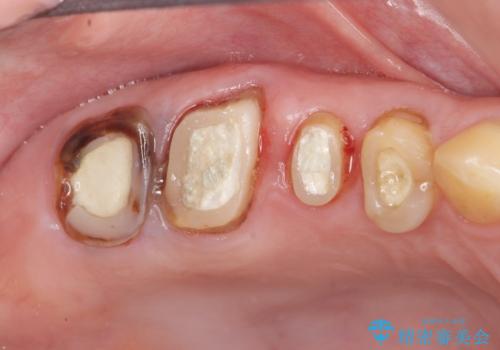

検査の結果、根管・クリアランス・虫歯といった複合的な問題が認められ、以下のような治療計画を進めることとしました。

クラウンの製作スペースの付属 →歯周外科によるスペースの確保

機能の回復・再感染の予防 →精密なジルコニアクラウンの作製